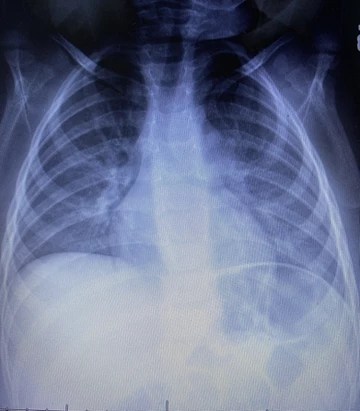

We went back to the pediatrician Friday morning. He was swabbed for COVID-19 and I requested a chest X-ray to rule out pneumonia from possibly aspirating his lunch when he vomited. Although very unlikely, our pediatrician complied. Two hours later we were given the X-ray read of bronchiolitis. A viral infection. Pediatrician advised for us to rest and monitor symptoms for continued fever or any more nose bleeds. Saturday, our son appeared to be getting better. He was tired, temperature hovering around 100.0 F, but he had an appetite. He drank Gatorade and ate Doritos. He slept much of the day in short naps.